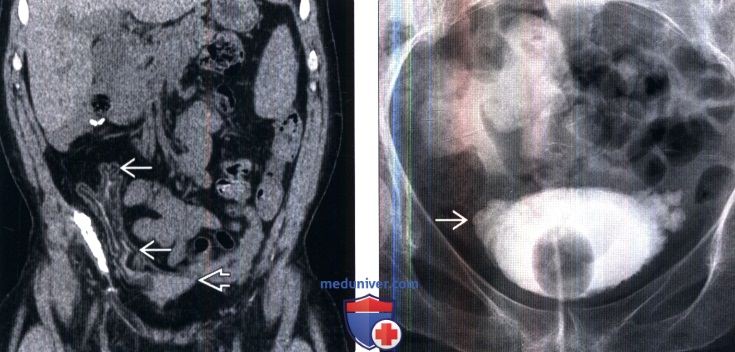

Изображения КТ конкрементов мочевого пузыря